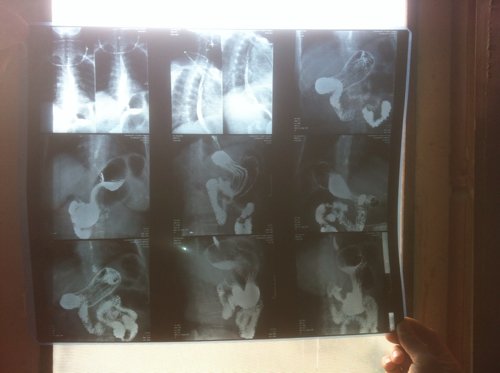

医生:我母亲58岁,20年老胃病了,胃口处有疼痛感饭量也不行,五个月前做了检查(检查结果在下面)

医生:我母亲58岁,20年老胃病了,胃口处有疼痛感饭量也不行,五个月前做了检查(检查结果在下面),现在疼痛感有所缓解,不过还是感觉不舒服,医院开的药是胶体果胶铋胶囊每天六粒;奥美拉唑肠溶胶囊每天两粒,复方阿嗪米特肠溶片每天两粒,问一下医生是不是换一下药还是做进一步的检查,谢谢